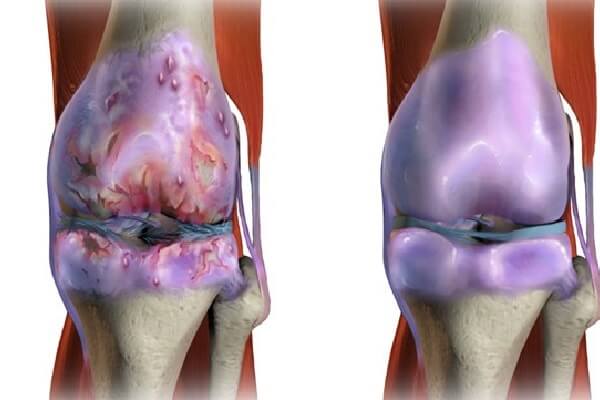

در افرادی که مبتلا به آرتروز شدید هستند، غضروف در یک یا چند مفصل به طور شدید یا کامل از بین رفته است.

اصطکاک و سایش استخوان ها در مفصل می تواند علائم شدیدی ایجاد کند، مانند:

– افزایش تورم و التهاب

ممکن است مقدار مایع مفصلی یا زلاله (سینوویال Synovial fluid) در مفصل افزایش یابد.

به طور معمول وجود این مایع به کاهش اصطکاک هنگام حرکت کمک می کند ولی اگر مقدار آن بیش از حد طبیعی شود، می تواند باعث تورم مفصلی شود.

قطعات خرد شده غضروف نیز ممکن است در داخل مایع سینوویال شناور شده و درد و تورم را افزایش دهند.